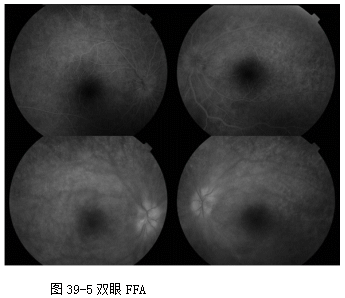

OCT(2012-7-31,本院): 双眼后极视网膜各层高反射点,IS/OS和ELM消失, RPE较毛糙。(见图39-3和图39-4)

FFA(2013-7-31,本院): 双眼视网膜动静脉充盈时间正常范围,视网膜后极和中周荧光轻度渗漏, 视乳头荧光渗漏,边界模糊——考虑“双眼葡萄膜炎? ”(见图39-5)